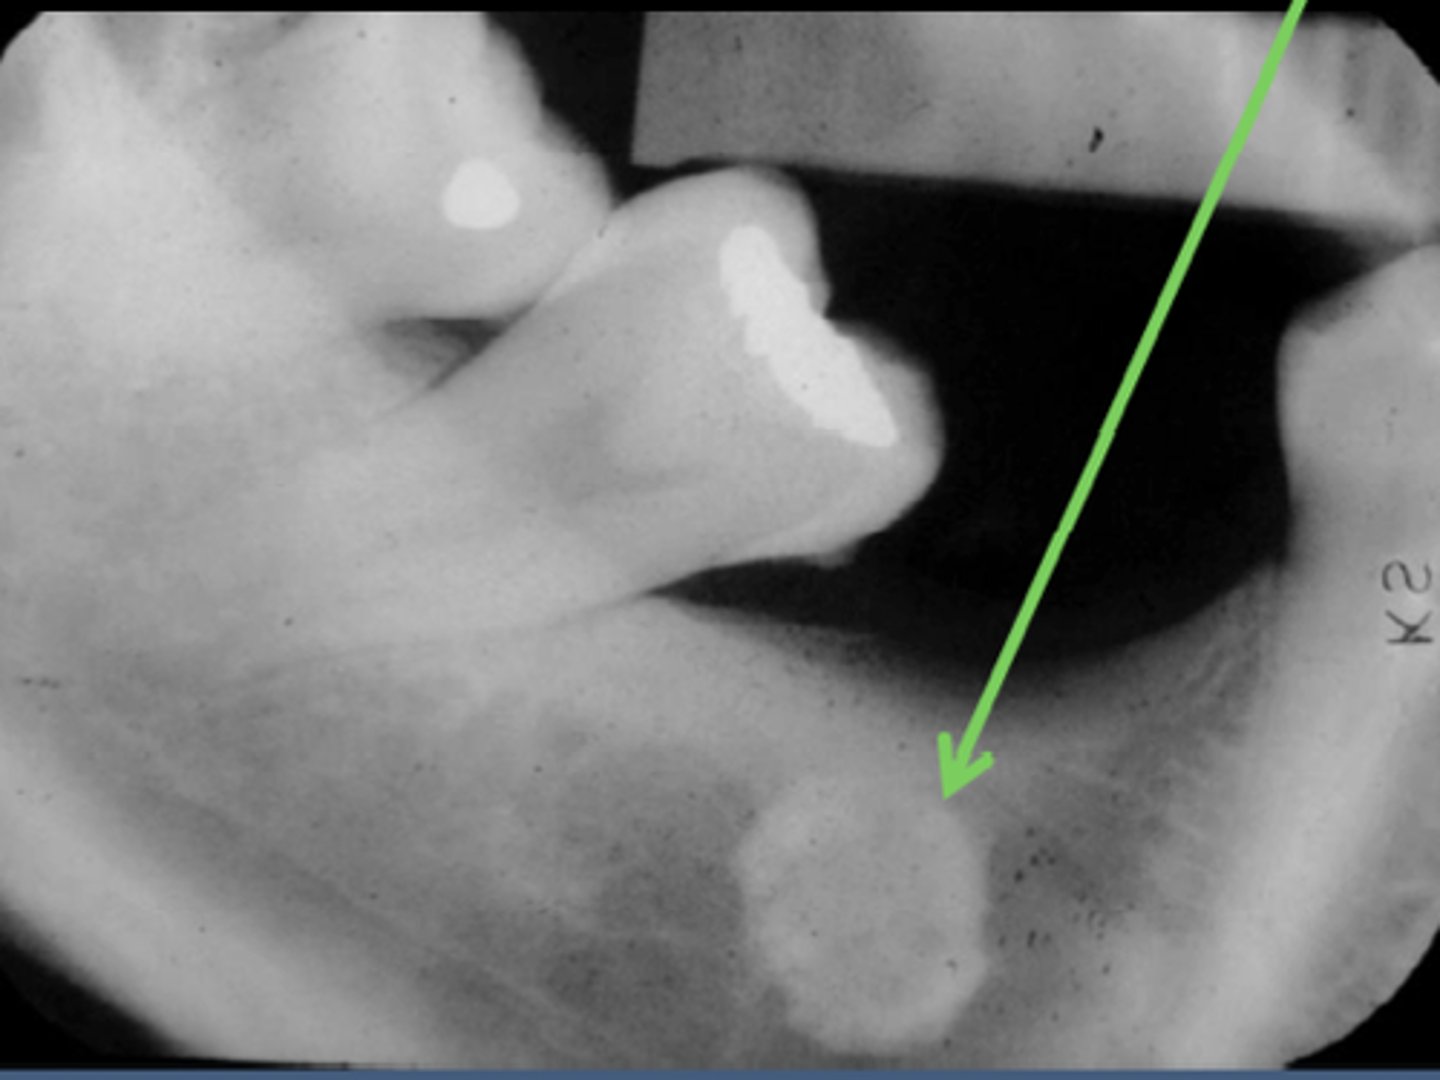

what is this?

what is this radiolucent area in the image?